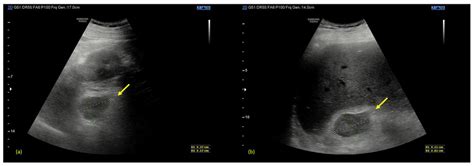

• waterhouse friedrich syndrome radiology